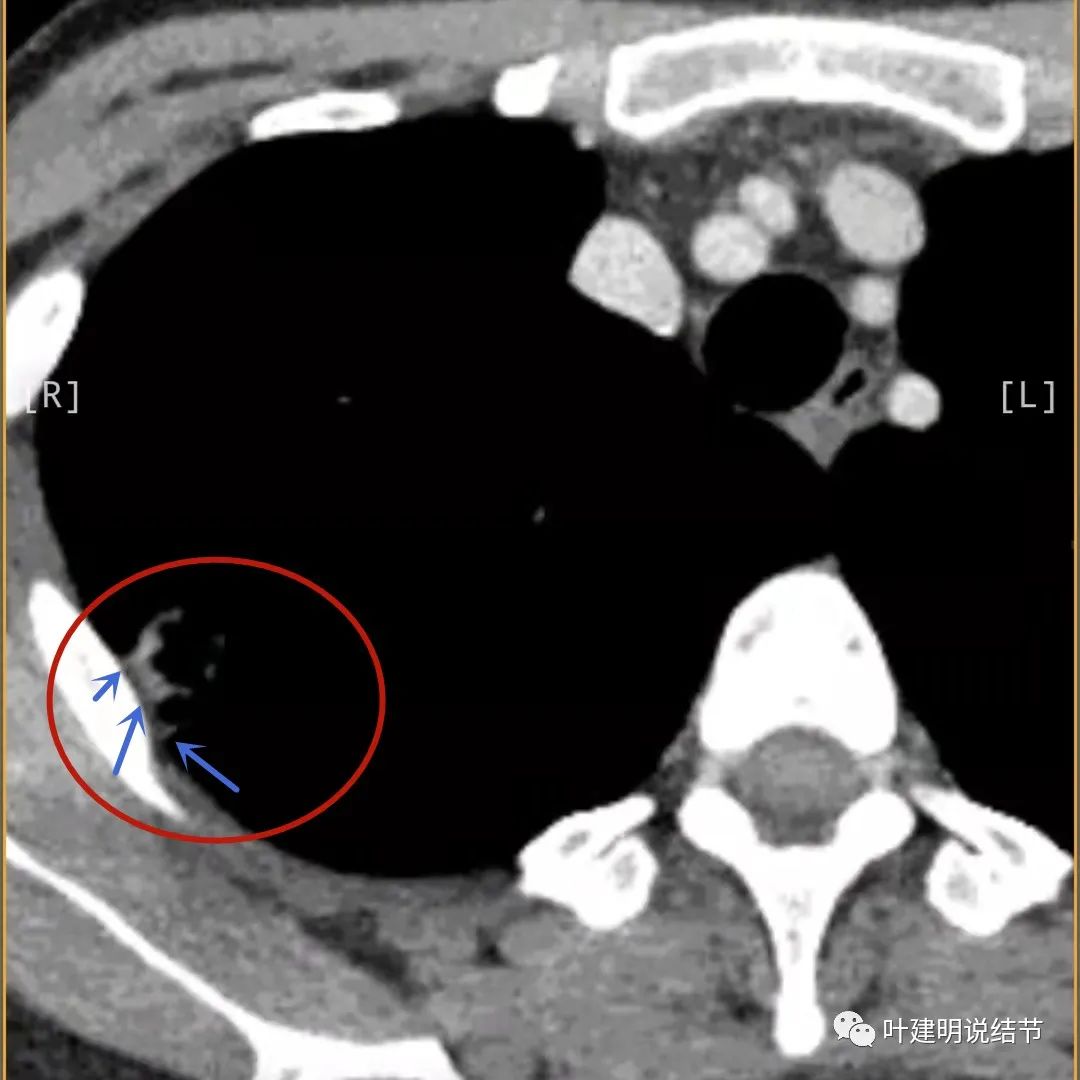

病灶邻近胸膜异常增厚(蓝色箭头)

有卫星灶(绿色箭头),邻近胸膜明显增厚,且模糊,边不清

邻近胸膜增厚